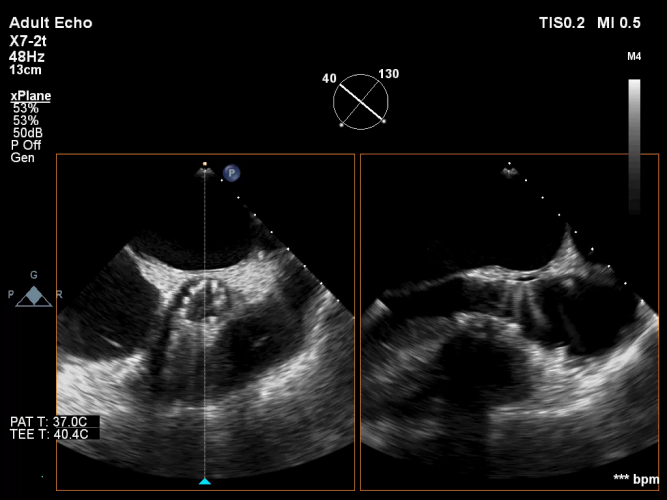

术后即刻评估:

术后平均压差在6mmHg左右,几乎无反流,瓣膜正常工作。